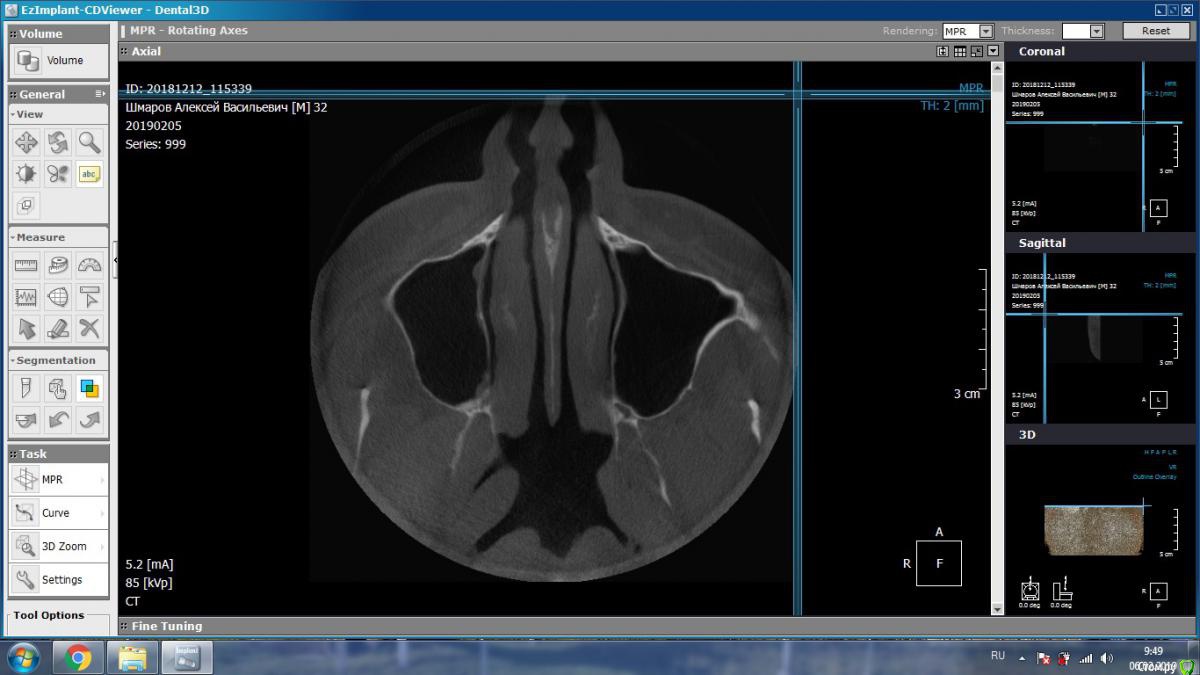

DmitrySH Опубликовано 5 февраля, 2019 Поделиться Опубликовано 5 февраля, 2019 Такие подойдут? В Аксиальной проекции покажите еще несколько срезов Ссылка на комментарий

aleks.k Опубликовано 6 февраля, 2019 Автор Поделиться Опубликовано 6 февраля, 2019 Срезы Ссылка на комментарий

aleks.k Опубликовано 6 февраля, 2019 Автор Поделиться Опубликовано 6 февраля, 2019 Еще один срез, может быть более удачный чем первые в этой проекции Ссылка на комментарий

DmitrySH Опубликовано 6 февраля, 2019 Поделиться Опубликовано 6 февраля, 2019 Срезы Очень хорошо. Теперь как первые три, но увеличить 16 зуб. Остальные нам мало интересны, пазуха тоже Ссылка на комментарий